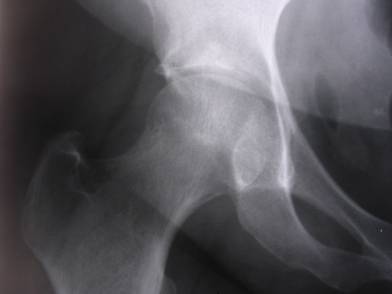

Chronic right hip pain